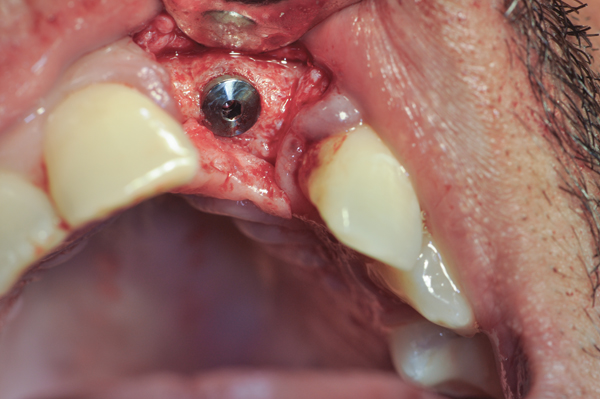

Fig 11. An implant was placed in regenerated bone.

Figure 11

Fig 14. An implant was inserted in regenerated bone.

Figure 14